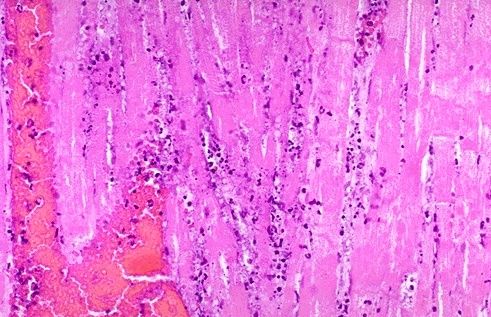

- This myocardial infarction is about 3 to 4 days old. There is an extensive acute inflammatory cell infiltrate and the myocardial fibers are so necrotic that the outlines of them are only barely visible